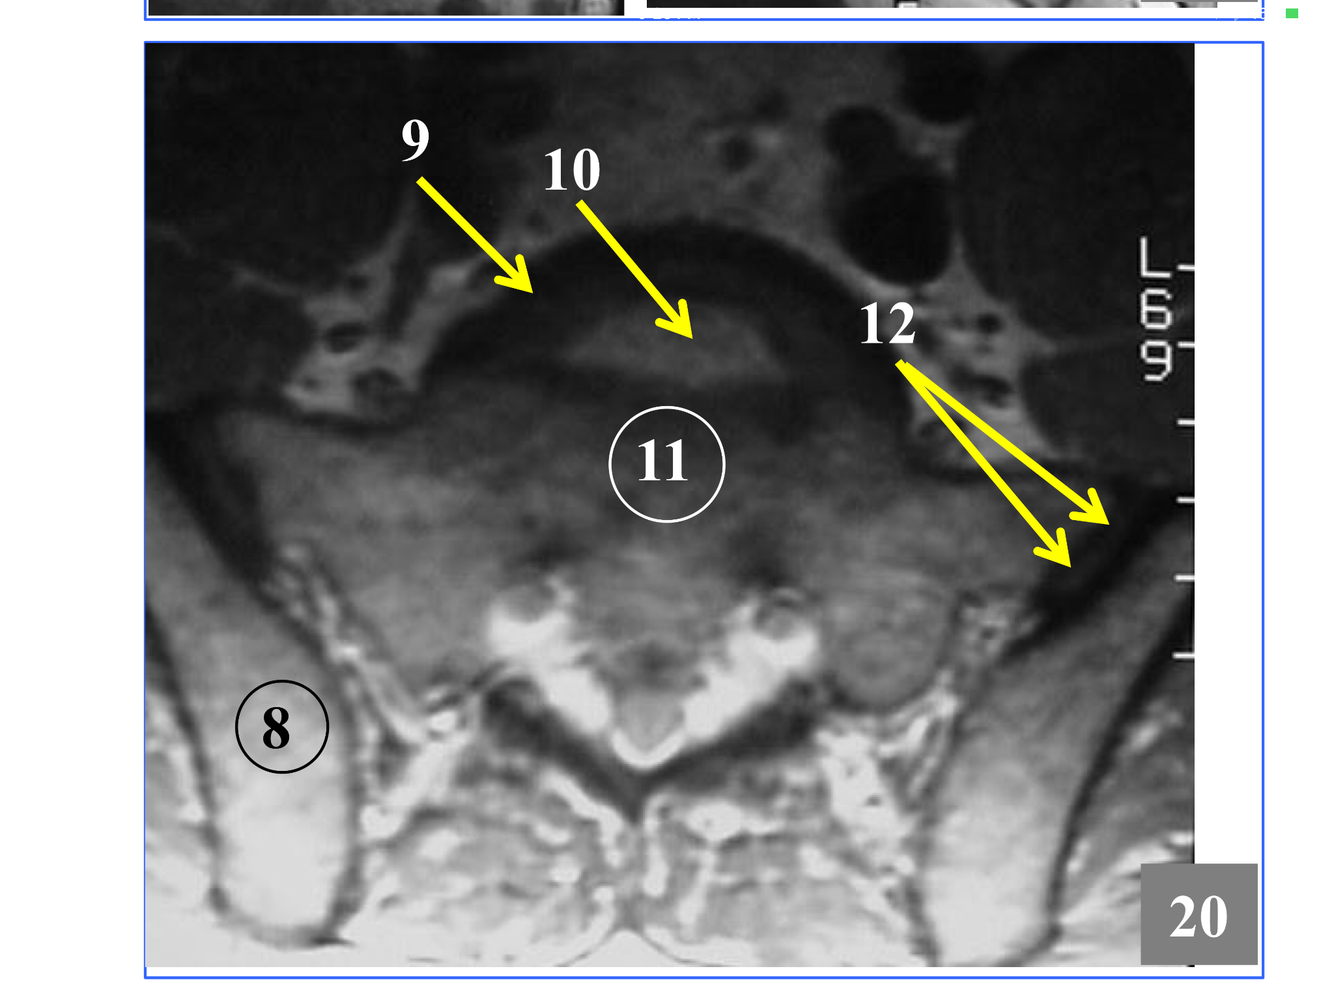

*Although the transverse process is not seen, the tubercle articulates with the transverse costal facet on it.

* Not seen in its entirety